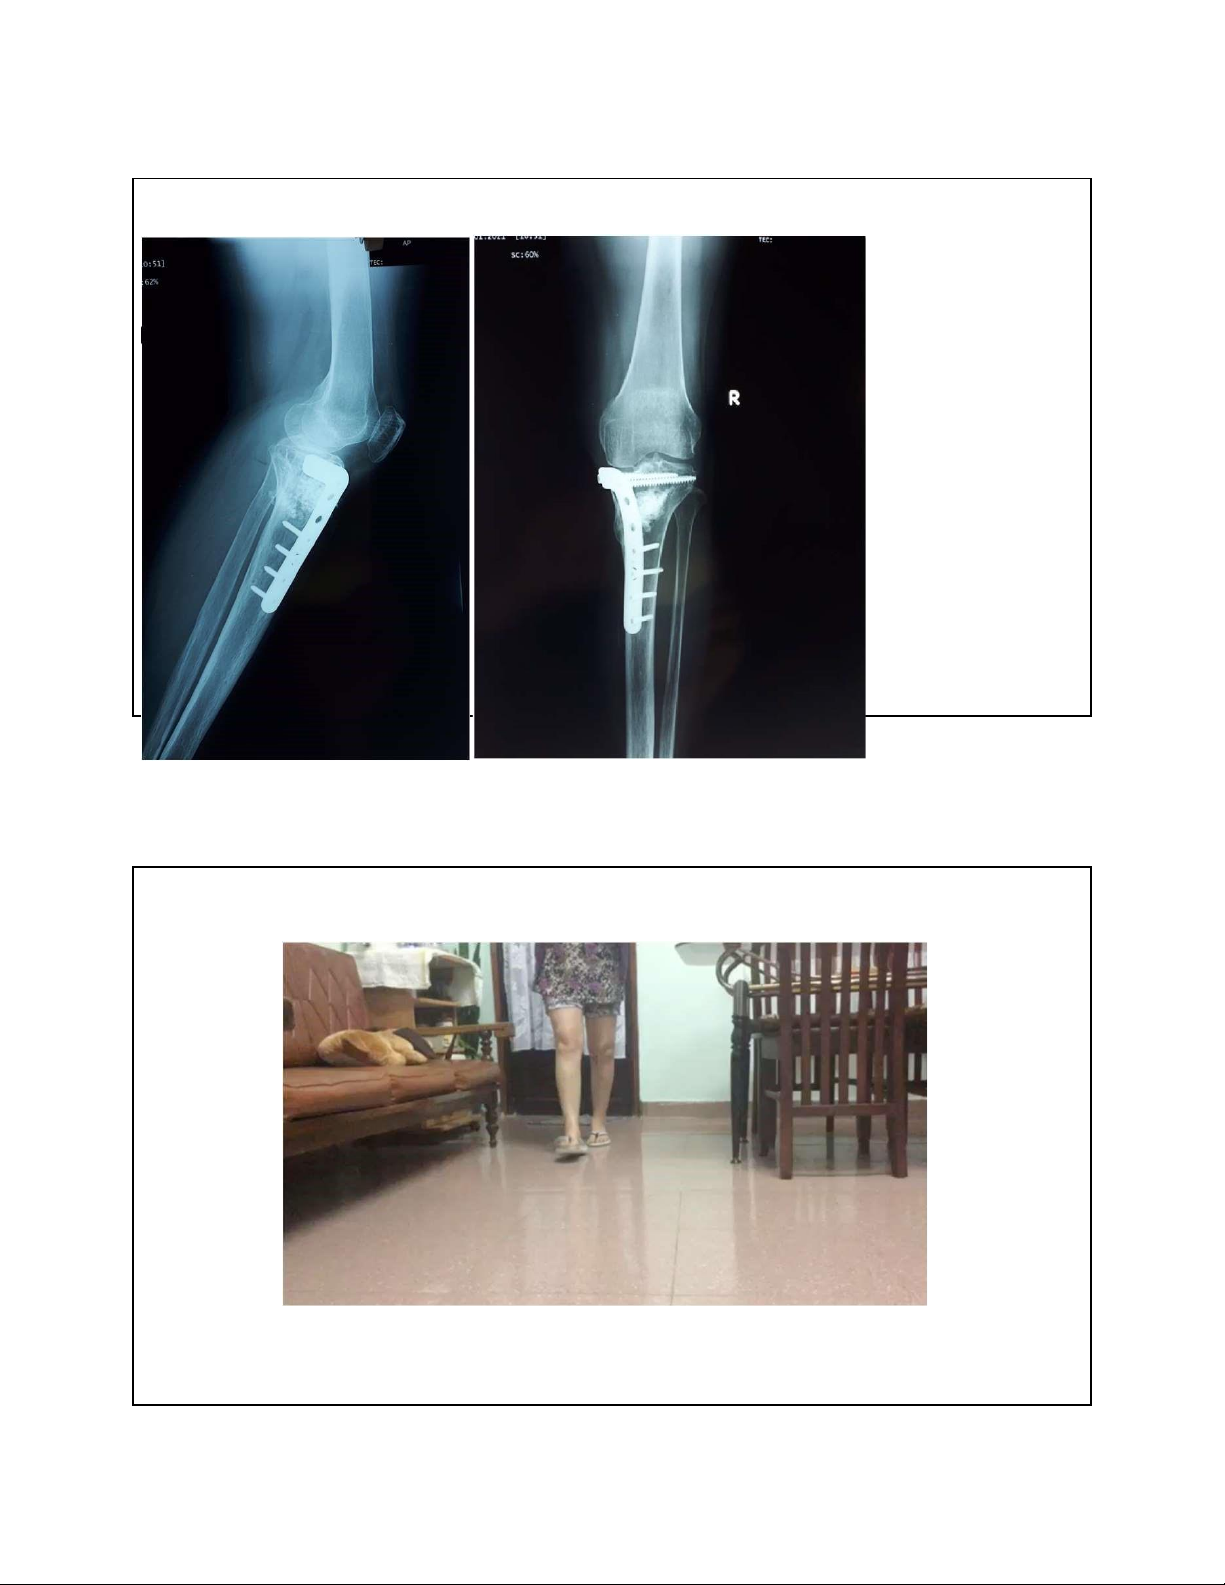

Vẹo trong(varus) trước và sau cắt xương 30 lOMoAR cPSD| 22014077 7/15/2023 Bn nữ 58t, gãy mâm chày 14th • Thay khớp hay bảo tồn khớp? 31 Chân vẹo trong sau mổ KHX 32 lOMoAR cPSD| 22014077 7/15/2023 33 lOMoAR cPSD| 22014077 7/15/2023 1 năm sau mổ 34 Dáng

i bình thường, trục thẳng và không au 35 lOMoAR cPSD| 22014077 7/15/2023 Thay khớp •Thay khớp 1 phần •Thay toàn phần 36